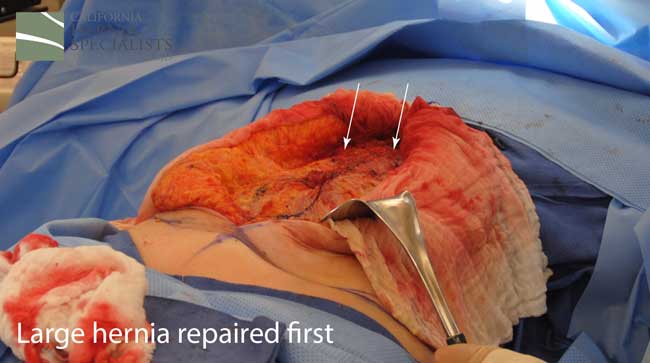

This initial CAT scan image shows why the hernia repair continued to fail. There is very weakened muscle in the middle of the abdomen with most of the healthy muscle several inches away on each side. More likely than not, the prior surgeon simply sewed the meshes into this unhealthy layer of fascia instead of bringing together the normal, healthy muscle.

After this CT scan was obtained, a lengthy discussion with the patient was undertaken to explain the reasons for the prior hernia repair failures, and to explain all the options. By simply returning to the operating room and putting in more mesh, and sewing it to unhealthy muscle, we would not be actually repairing the hernia.

The more complete approach would be to bring healthy muscle together at the mid line. Only after the muscle is repaired completely, can a mesh be used to SUPPORT the muscle repair. Meshes should not be considered a bridge from healthy muscle to healthy muscle. Instead mesh should be used as a reinforcement of a correct hernia repair.

This technique requires more surgical time, recovery time, and usually several days in the hospital. However, this patient chose to proceed with the open hernia repair. Below are some of the pictures from his surgery as well as post operative CT scan image and photos of the patient.

Because this patient had failed two prior surgeries, we performed a complex open hernia repair on him. This repair included a technique called ‘component separation’, where the oblique muscles on the sides of the abdomen, are partially released, or cut, to allow the rectus muscles to be pulled back together in the middle of the abdomen.

Since the abdominal muscles were weakened, we placed a sheet of biologic mesh under the muscle in the middle at the area of the hernia hole, closed the muscle over this mesh, then placed another mesh on top of the muscles which were closed. This provided him with three layers of repair.